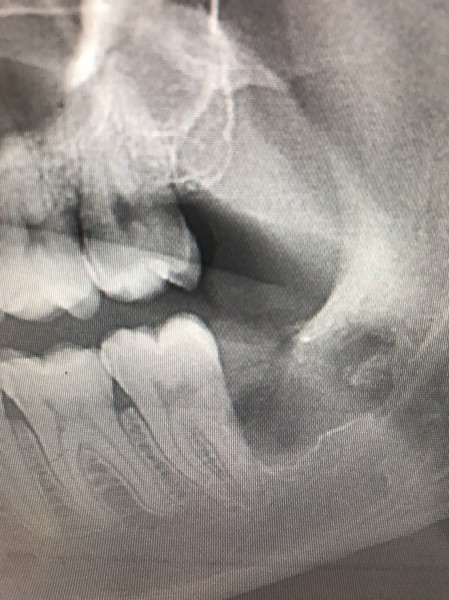

Case002 – 親知らず抜歯

親知らず抜歯のBefore/After

他院では大学病院での治療を勧められたという難しい抜歯ですが、当院では初診時に抜歯いたしました。

また、厚生労働省認可の骨再生療法(CGF)を使用できるため、親知らずの抜歯後の痛みを通常よりも大幅に軽減することができます。

担当:理事長 佐藤悠野